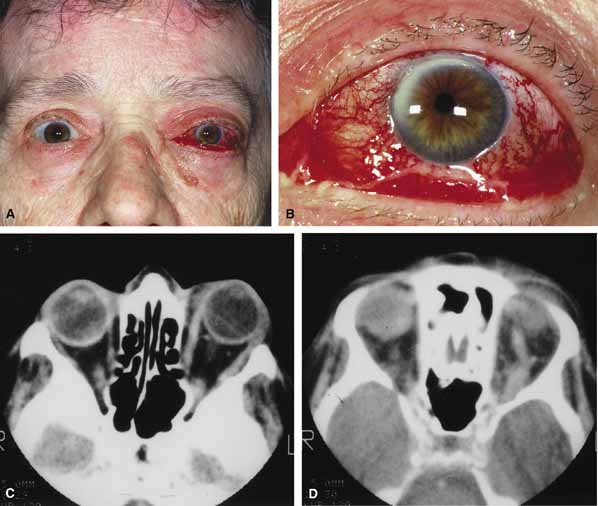

ORBITAL CELLULITIS Orbital cellulitis is the model for acute inflammation and a major cause of orbital inflammation in adults.2 It is characterized by a rapid development (over 1 to 2 days) of inflammatory signs and symptoms. These include: eyelid swelling, redness, warmth, pain, conjunctival injection, chemosis, proptosis, and mobility impairment with or without reduced vision. These patients generally feel unwell (malaise) and are febrile (Fig. 1A and 1B). The malaise and fever are key features in differentiating cellulitis from a rapid-onset nonspecific orbital inflammation (pseudotumor) and should be obtained from the patient's history. The majority of orbital cellulitis is secondary to extension from an adjacent sinus infection (Fig. 1C). Organisms gain access to the orbit directly through the thin ethmoidal bone, through congenital or acquired dehiscences in the thin orbital walls, pass through preexisting orbital foramina, pass retrogradely through the valveless venous orbital system, or along the veins as a periphlebitis. Orbital cellulitis may also be secondary to an endophthalmitis, systemic bacteremia (e.g., after dental work), infection of a nearby skin wound, dacryocystitis, or penetrating trauma. The history and physical examination are crucial in distinguishing between preseptal and true orbital cellulitis. The orbital septum delineates the anterior eyelid soft tissue from the orbital soft tissue. Infections anterior to the septum are classified as preseptal cellulitis while those posterior to the septum are termed orbital cellulitis. Recognition of true orbital involvement is important not only because of the threatened visual loss associated with the orbital involvement but also because of the potential for central nervous system complications including cavernous sinus thrombosis, meningitis, and death. Preseptal cellulitis is characterized by lid edema, erythma, and discomfort. Inflammation posterior to the orbital septum (orbital cellulitis) is heralded by the development of pain, chemosis, proptosis, motility disturbance, and visual deterioration. The extent of ocular involvement in preseptal and orbital cellulitis can be determined by assessing visual acuity, extraocular motility, pupillary reaction, color vision, confrontation visual fields, intraocular pressure, and optic nerve head appearance. Evidence of facial/head trauma or surgical wounds may be apparent. Constitutional signs such as fever, lethargy, and irritability should be sought. The examiner should assess for meningeal signs and neurologic defects. After the initial examination, the physician should follow patients with orbital cellulitis with at least daily assessments of visual acuity, motility, and pupil reaction. Progression of the disease process despite appropriate antibiotic therapy suggests abscess formation. Orbital abscesses may be either localized, diffuse, or subperiosteal (Fig. 1C). Subperiosteal abscesses most commonly occur along the medial wall and may expand rapidly, compromising optic nerve function even in the absence of many signs of infection.3–6 Several mechanisms may contribute to visual deterioration including direct optic nerve compression, elevation of the intraorbital pressure, and proptosis causing a “stretch” optic neuropathy. Clinically, the eye typically is displaced away from the subperiosteal abscess, and orbital imaging shows a convex mass adjacent to the involved sinus. Orbital infection with potential orbital abscess formation occurs when bacteria break through the periorbita and gain access to the extraoconal or intraconal space. Diffuse or localized orbital abscess formation may also lead to visual loss through an increase in intraorbital pressure, posterior ischemic optic neuropathy, optic nerve inflammation, or vasculitis. Acute visual loss in the presence of an orbital infection is almost always a surgical emergency in which immediate drainage of the abscess is required to save vision. Continued posterior extension of the infection may result in an orbital apex syndrome, decreased function of cranial nerves,2–6 thrombosis of the cavernous sinus, and even death. Hallmarks of cavernous sinus thrombosis include cranial neuropathy and central neurologic impairment.7 Organisms responsible for orbital cellulitis vary widely and may include Staphylococcous aureus, Streptococcus species, as well as a mixture of aerobes and anaerobic organisms. Recent studies indicate that streptococcus is the most common cause of orbital cellulitis associated with sinusitis in children.8 With increasing age the pathogens increase in complexity. In patients older than 15 with subperiosteal abscesses, polymicrobial infections are typical with anaerobes cultured in every case.5 Orbital imaging in the axial and coronal plane should be obtained in all patients suspected of having orbital cellulitis. Computed tomography (CT) is preferred to magnetic resonance imaging (MRI) because the orbital tissues have higher contrast and bone is well visualized. Axial CT views allow evaluation of the medial orbit and ethmoid sinuses, whereas coronal scans image the orbital roof, floor, frontal, and maxillary sinus. A subperiosteal abscess appears as a homogeneous opacification between the orbital wall and the displaced periorbita.6 Contrast agents are not necessary to visualize a subperiosteal abscess. Management of orbital cellulitis is dictated by the rapidity of onset. Oral antibiotics may be appropriate for mild cases whereas intravenous antibiotics are required for more fulminant cases. Antibiotic coverage should be broad spectrum and include coverage for gram-positive organisms and anaerobes. Examples include cloxicillan and clindamycin or a late-generation cephalosporin and clindamycin. In those patients allergic to penicillin agents, erythromycin and clindamycin or vancomycin and clindamycin are considerations. Most patients with orbital cellulitis also benefit from a nasal decongestant as well as an oral decongestant and warm compresses to the affected site (10 minutes out of every hour). Daily or more frequent reexaminations are required depending on the fulminancy of the disease. Once antibiotics are initiated, a 24-hour wait-and-watch period is generally observed (unless the process is aggressive and rapidly developing). If there is no progression at 24 hours and the vision is stable, continued observation is appropriate. If the orbital cellulitis is rapidly developing and fulminant, frequent assessments (every 2 to 4 hours) are required. If the vision, motility, or neurologic status is deteriorating, immediate surgical intervention may be required. The indication for surgery in a patient with orbital cellulitis has been controversial over the years. The simple presence of a subperiosteal abscess (SPA) was at one time an indication to drain but this is no longer always the case. Providing the vision is normal, the SPA may resolve with medical management. The clinical course, and not the radiographic appearance should dictate management.5,6,9 Surgical therapy may be influenced by many factors including the visual status, size, and location of the SPA; intracranial complications; the sinus involved; the presumed pathogenesis, and the anticipated bacterial response to antibiotic treatment.10 Immediate drainage of SPAs and sinuses is recommended for patients of any age whose vision is compromised. Urgent drainage (as soon as practical) should be considered for large SPAs, extensive superior or inferior abscesses, intracranial complications at the time of presentation, frontal sinusitis where the risk of intracranial extension is increased, and in those suspected of having anaerobes (postdental procedures). However, cookbook approaches should never take the place of good clinical judgement and therapeutic decisions regarding early drainage versus medical management with observation are ultimately up to the managing physician.10 Older children (older than 9 years of age) and adults benefit from early surgical drainage. Although surgical treatment does not guarantee rapid resolution, a complicated course is more likely without it.10 Abscesses may also develop within the intraconal space. The prescence of an abscess within the orbital tissue coupled with any signs of visual loss, afferent pupillary defect, or a significant motility defect should prompt emergent surgery. If visual acuity is stable and extraocular motility essentially full, initial treatment may consist of empiric antibiotic therapy and close observation with serial CT scans. The prescence of neurologic symptoms such as altered mental status or seizures implies intracranial extension with potential intracranial abscess. Infection may spread from the sinuses to the intracranial cavity via retrograde thrombophlebitis, directly through osteitic bone or from congenital or acquired bony defects. In the past, intracranial abscess formation had a poor prognosis with a high mortality rate. Successful management of suppurative abscesses requires early recognition of the disease process, intravenous antibiotics, serial neuroimaging, and surgical management of at least the orbit and sinus disease and often the intracranial disease.11 PHYCOMYCOSIS (RHINO-ORBITAL MUCORMYCOSIS AND ORBITAL ASPERGILLOSIS) Rhino-orbital mucormycosis, a fungal infection of class Phycomycetes and order mucorales, is notable for its high morbidity and mortality.12,13 Orbital involvement is an acute, aggressive, and often lethal infection if not recognized early. Phycomycetes (common bread molds) are ubiquitous fungi occurring in soil, air, skin, body orifices, manure, and food including fruit.13 Inoculation occurs by inhalation reaching the nasopharynx and oropharynx. At this stage most patients are able to contain the disease. However, individuals whose cellular and humoral defense mechanisms have been compromised by disease or immunosuppressive treatment may not be able to generate an adequate response. The fungus may then spread to the paranasal sinus, orbit, meninges, and brain by direct extension.13 Mucormycosis preferentially involves blood vessel walls resulting in vascular occlusion, thrombosis, and infarction.14 This frequently affects the ophthalmic artery and in more serious cases may involve the internal carotid artery and cavernous sinus. Although there have been a few reports of mucormycosis occurring in healthy individuals, virtually all other patients have had previous severe underlying disease. The patient most vulnerable to this infection is an one with uncontrolled diabetes with ketoacidosis. A host of other conditions also predispose patients to the disease including: multiple myeloma, lymphoma, organ transplantation with immunosuppresion, chemotherapy, corticosteroid treatment, acquired immunodeficiency syndrome, etc.(Fig. 2A).12–14 Mortality is extremely high for patients with phycomycosis infection, and successful treatment is contingent on early recognition and prompt treatment. A characteristic pattern of clinical symptoms and signs occurs, the recognition of which should lead to the immediate institution of antifungal treatment and possible surgical intervention to increase the patient's chances of survival. Early diagnosis while the disease is still somewhat anatomically confined is essential for a more favorable outcome.12–14 Characteristic features of orbital mucormycosis include an immunocompromised patient with sinusitis, pharyngitis or nasal discharge who develops cellulitis of the face or lid. Signs and symptoms include orbital/periorbital pain, acute proptosis, abrupt visual loss, orbital apex syndrome with acute motility changes (external ophthalmoplegia), pupillary changes (internal ophthalmoplegia), ptosis, and decreased corneal sensation. Infarction of tissue results in black eschar formation of the skin, nasal mucosa and hard palate (Fig. 2A and 2B).12,13 With intracranial extension, the patient generally become obtunded, develops convulsions, contralateral hemianaesthesia or hemiplegia, and lapses into coma. CT scanning demonstrates an orbital mass often with bone destruction and sinus involvement (Fig. 2C and 2D). The diagnosis is confirmed by biopsy of involved tissue with demonstration of characteristic nonseptate, large, branching hyphae, which can be seen on routine hematoxylin and eosin stains. Material should be submitted for both frozen and conventional paraffin-embedded sections. Frozen sections are not always definitive and the surgeon must have considerable confidence in the skill of the pathologist. 13 Management includes: (1) early definitive diagnosis; (2) correction of any underlying metabolic disturbance; (3) wide local excision with debridement of all involved and devitalized oral, nasal, sinus and orbital tissue; (4) establishment of adequate sinus and orbital drainage; (5) daily irrigation and packing of the involved orbital and paranasal areas with amphotericin B; and (6) intravenous amphotericin B.12,13,15 The extent of surgical excision should balance the degree of morbidity and mutilation against the life-threatening risk this organism represents. In limited cases, surgical excision may be confined to those tissues clearly infarcted. Should infection be extensive as demonstrated by widespread necrosis, then aggressive surgery, including exenteration of the orbit and any involved paranasal sinuses, may prove necessary and lifesaving.13 ORBITAL ASPERGILLOSIS Aspergillus, a fungus of the Ascomycetes class, is a common environmental organism that may colonize the aerodigestive tract. Although widespread, the fungus has a low intrinsic virulence and clinically apparent aspergillosis is rare in the immunocompetant host. Invasive aspergillosis, similar to mucormycosis, occurs more often in the immunocompromised host, including patients undergoing transplantation or steroid therapy, neutropenic patients undergoing chemotherapy, alcoholics, patients with diabetes, and patients with acquired immune deficiency syndrome (AIDS).16–20 Orbital involvement may be slowly progressive or abrupt in onset with orbital inflammation, proptosis, pain, ophthalmoplegia, and sudden loss of vision.16,19 Fulminant aspergillus infection of the nose, paranasal sinus, and orbit often associated with intracranial extension has been reported with increasing frequency in immunocompromised individuals.17,18 In these patients, local invasion of the sinus mucoperiosteum produces a rapidly progressive gangrenous necrosis.18 With bone destruction, infection may extend into the orbit and intracranial cavity; the latter has a poor prognosis. The fungus may also spread by hematogenous routes.17 Imaging studies reveal sinus involvement, heterogenous soft tissue masses with bony erosion, and calcification.16 A definitive diagnosis of aspergillosis is based on tissue biopsy and fungal cultures. Treatment of invasive sino-orbital aspergillosis involves aggressive surgical debridement combined with a systemic antifungal agent. Intravenous amphoticin B has been the mainstay of medical therapy but toxic side effects, especially renal, require discontinuing the medication in some patients. Newer systemic antifungal agents include liposomal amphotericin B (fewer renal toxic effects) and oral intraconazole.21–24 Adjuvant local irrigation of amphotencin B has also been recommended.24 For patients unable or unwilling to undergo surgery, intralesional injection of amphotericin B has been used successfully as palliative treatment.25 Despite aggressive therapy, the mortality in those with invasive sino-orbital aspergillosis remains high.17 |